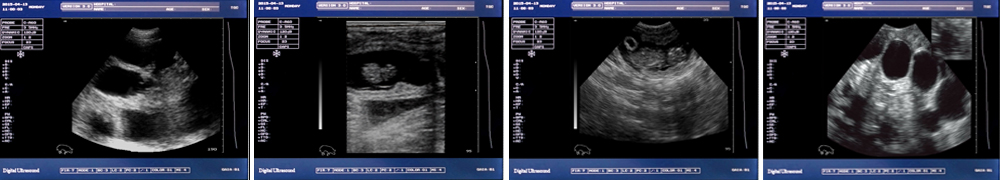

● 顯示模式:B、B/B、B+M、M、4B;

一流的數(shù)字成像技術 圖像更清晰